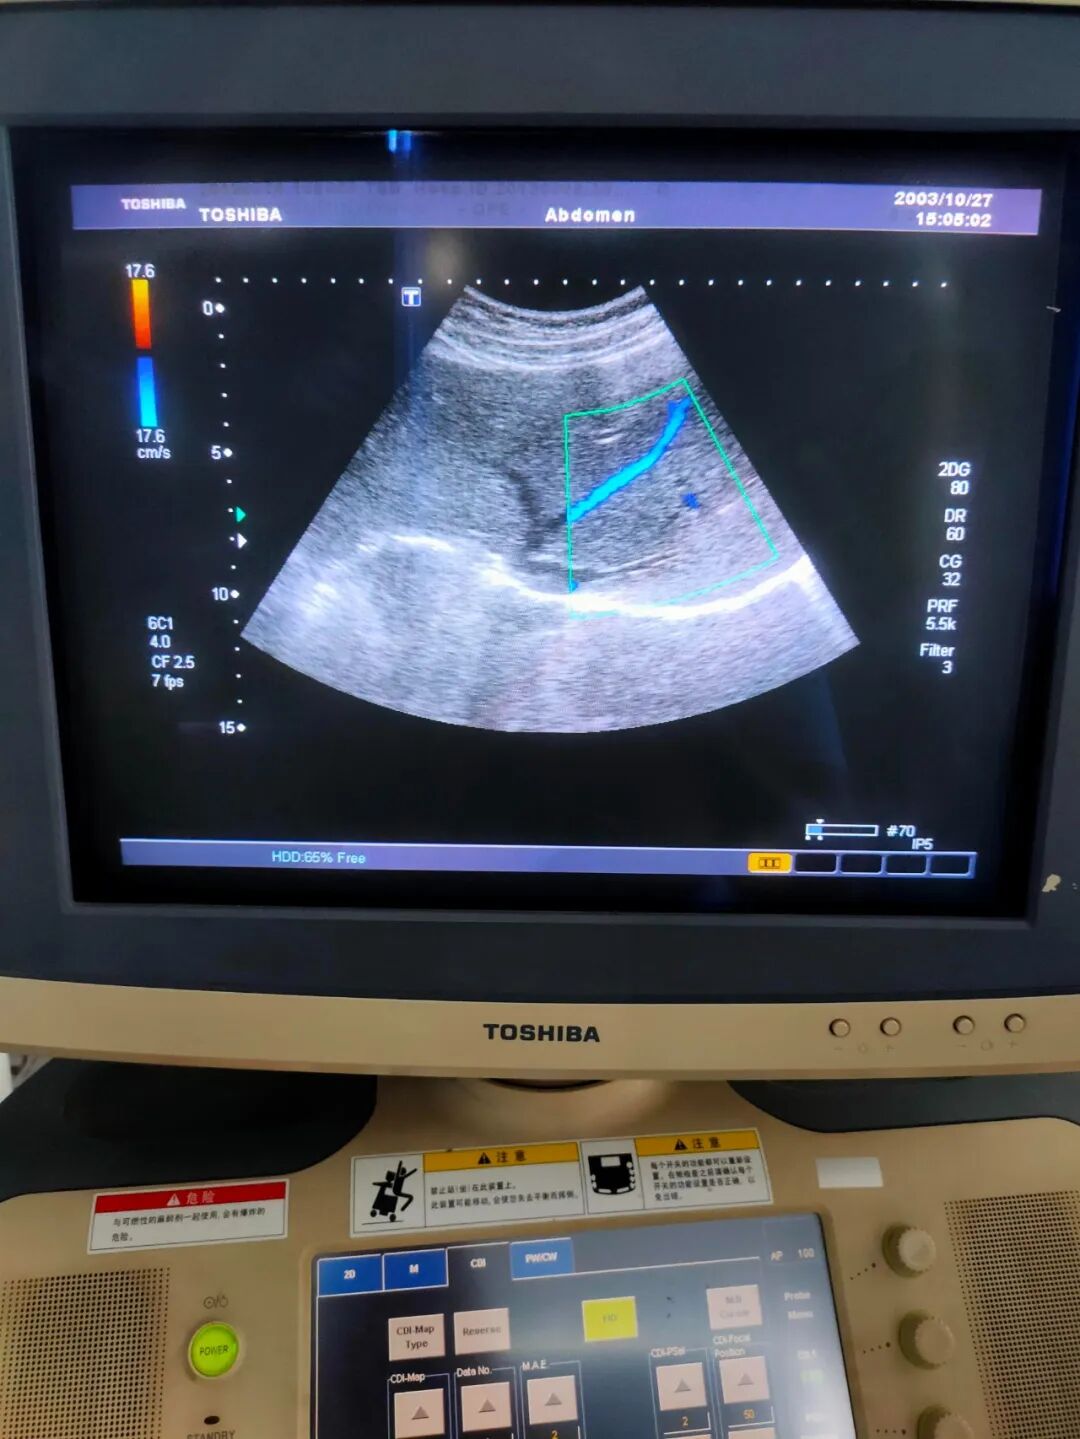

机器类型:东芝腹部探头

(2)上机检测声头摔坏,晶体打火,声头坏,外壳塞满硬胶,无法完整拆出。

更换声头,更换外壳。上机后图像正常。